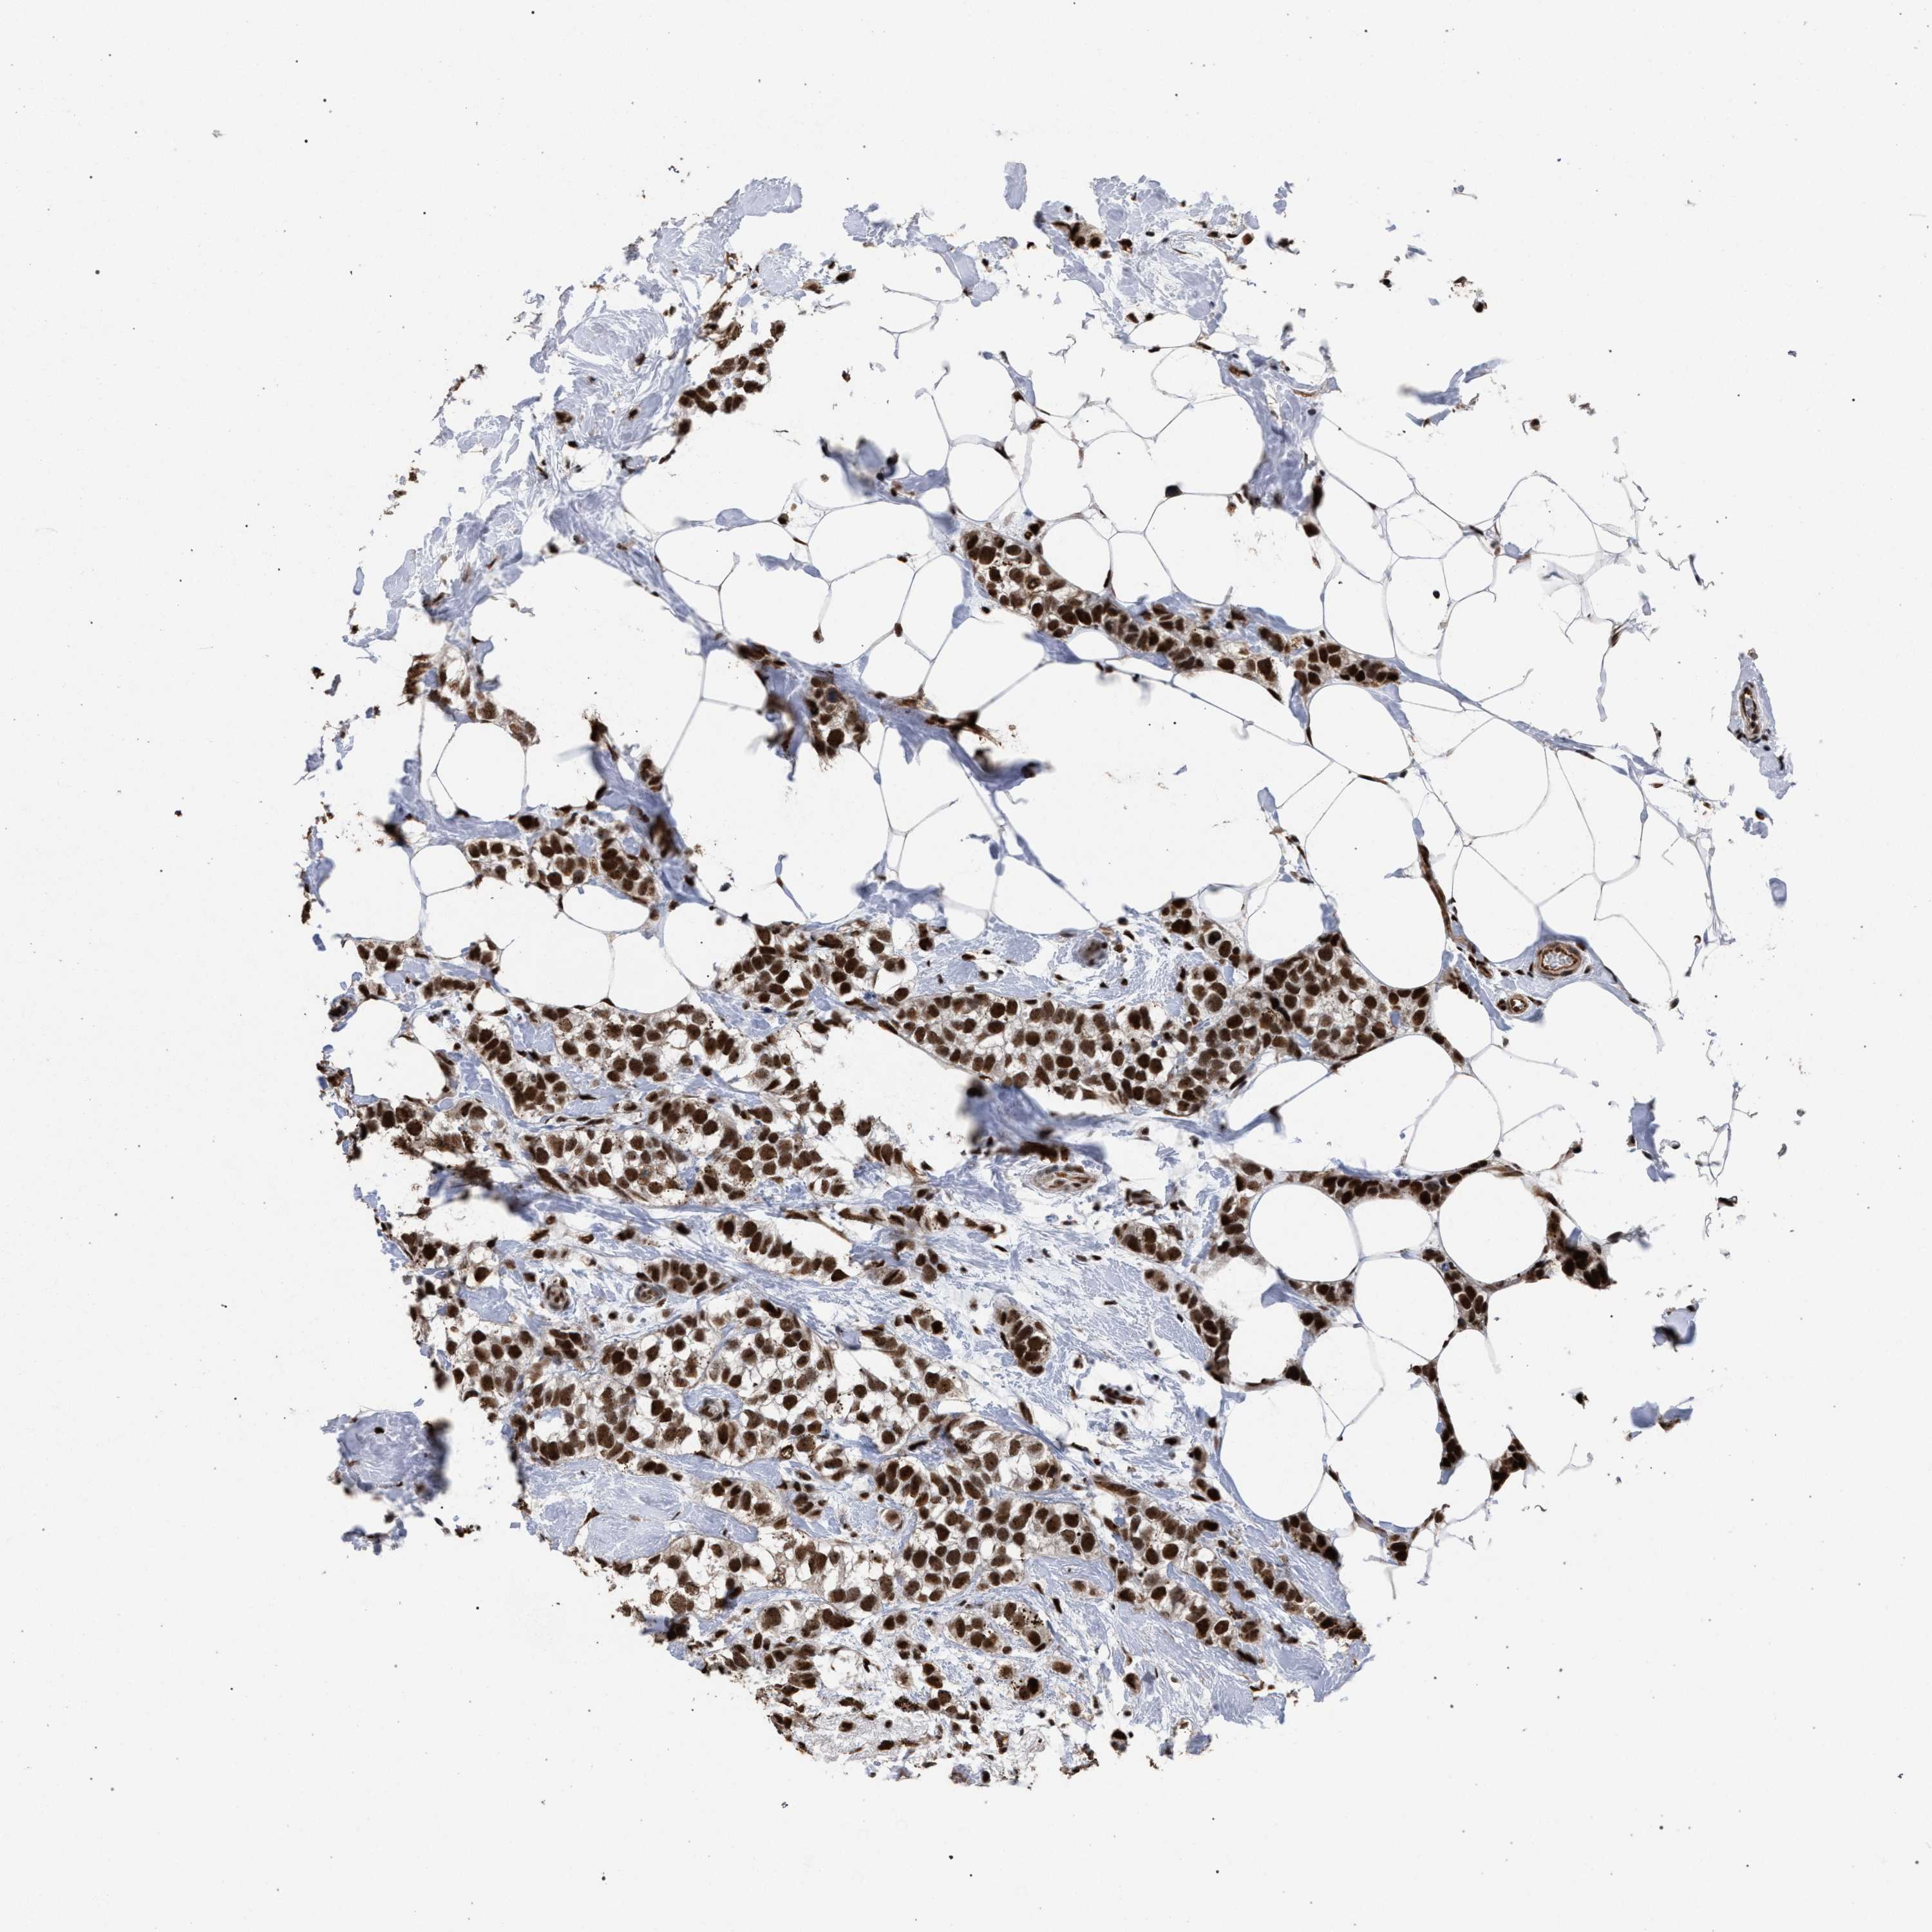

BRCA TCGA BRCA VALIDATION PROTEIN EXPRESSION

ANTIBODIES

AND

VALIDATION